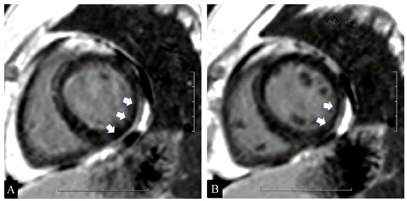

①常规指标。血常规:白细胞12.82×109/L,余无异常;谷丙转氨酶57 IU/L。NT-proBNP、心肌酶谱和TnI、肿瘤标志物、甲状腺功能正常。②炎症指标。C反应蛋白、红细胞沉降率、抗链球菌溶血素O、类风湿因子正常;EB病毒、巨细胞病毒核酸定量检测均正常。③免疫指标。ANA、抗SS-A、抗SS-B抗体均阴性,免疫球蛋白G 17.200 g/L升高,补体正常。血管炎三项、抗磷脂综合征检测均正常;淋巴细胞亚群:CD19+B淋巴细胞百分比28.88%(升高);眼科检查:滤纸试验右眼10 mm/5 min,左眼5 mm/5 min。④心电指标。DCG:房室传导功能恢复。电生理检查:以400 ms的频率起搏,窦房结恢复时间(sinus node recovery time,SNRT)为803 ms,以350 ms的频率起搏,SNRT为692 ms;房室结前传不应期:220 ms;房室结前传文氏点230次/min;窦律下希氏束至心室(His-to-ventricular,H-V)间期延长至65 ms,阻滞部位在HB下;未见房室结双径和房室旁道。⑤TTE。PASP正常;冠状动脉CT造影正常;心脏磁共振成像(magnetic resonance imaging,MRI):主动脉瓣轻中度关闭不全,心功能大致正常。心肌首过灌注未见明显异常;延迟扫描示左室侧后壁近段少许外膜侧强化。⑥心内膜心肌活检病理结果。光镜下见心肌细胞轻度肥大,空泡变性,间质纤维组织轻度增生,心肌非特异性改变(图3);电镜病理诊断:部分心肌细胞急性非缺血性损伤,不除外心肌炎累及(图4)。⑦胸部CT。双肺局部膨胀不全,部分伴钙化。血气分析(-)。呼吸功能:中-重度混合性通气功能障碍,小气道功能减退,肺弥散量轻-中度下降,气道阻力偏高,弹性阻力偏大。

心律失常性晕厥:DCG证实晕厥时三度、高度房室传导阻滞,电生理检查证实阻滞部位在希氏束(His bundle,HB)以下。自身免疫性心肌炎的诊断依据:①青年女性,慢性病程,自幼年具有自身免疫特征(双手皮肤溃疡),目前多系统受累(肺实质、肺血管、心包、心脏传导系统、心肌、眼、关节等),ANA及抗SS-A抗体阳性。②有乏力、活动后气短、心悸、晕厥症状。③心脏结构功能异常并能除外局灶性冠状动脉缺血。起病初期NT-proBNP升至675.35 ng/L,ECG示一过性肢体导联低电压、辅助检查显示一过性肺动脉高压、心包积液、胸腔积液,提示心功能受损。DCG示间歇性三度、高度房室传导阻滞,电生理检查示房室传导障碍。④心脏MRI(图5)示少许心包积液,延迟钆显像示左室侧后壁近段少许外膜侧强化,结合临床不能除外既往或潜在的心肌炎性病变伴局部心肌纤维化形成。⑤心内膜心肌活检光镜下见心肌细胞轻度肥大,空泡变性,间质纤维组织轻度增生,电镜下见部分心肌细胞急性非缺血性损伤,不除外心肌炎累及。⑥甲泼尼龙+环磷酰胺治疗后心脏病变的可逆性。